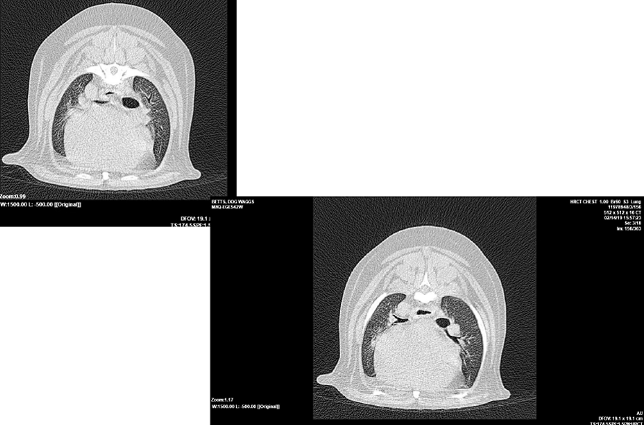

Little area of consolidation but nothing else significant

DX - chronic cough suspicions for airaway disease due to chronic unproductive cough

On left hand side (actually right ariway) airway is compressed

Wouldn’t be ablse to see mass on radiograph as heart borders block ti

Bronchoscopy - wouldn’t be able to see the mass - only see the collapse but not what caused it

CT is our bitch